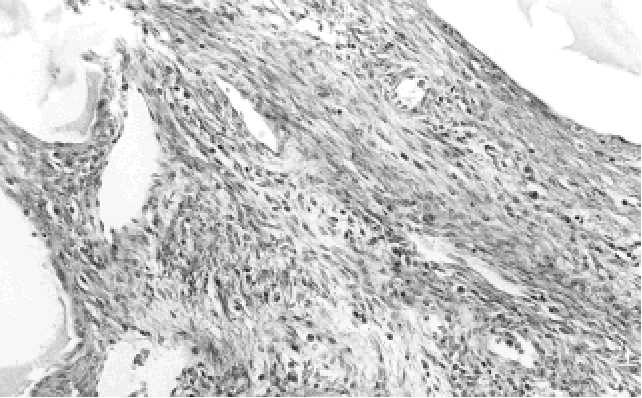

v cystickém nefromu nenachází. Cystický nefrom dětského věku bývá zpravidla bu- něčnější než cystické nefromy v dospělosti. U cystických nefromů v dospělém věku jsou někdy cysty vystlané atypickým světlobuněčným epitelem(227). Vzácně byl po- psán i vznik konvenčního světlobuněčného karcinomu v cystickém nefromu dospě- lého věku(227). V  8 publikovaných případech byla popsána malignizace cystického nefromu do nejrůznějších sarkomů. Jednalo se o nediferencovaný embryonální vře- tenobuněčný sarkom (6 případů), nízce maligní leiomyosarkom (1 případ) a  pleo- morfní vysoce maligní sarkom (1 případ)(23,300). Imunohistochemické  vyšetření.  Stroma  cystického  nefromu  reaguje  pozitivně s protilátkami proti kolagenu IV. typu, hladce svalovému aktinu a desminu. Ostatní imunohistochemické reakce nemají diagnostický význam. Elektronmikroskopické vyšetření. Epitelová v stelka cystického nefromu je vyba- vena krátkými mikrovily(92). Tang a spol. usoudili, že se tento epitel ultrastrukturálně podobá epitelu sběrných kanálků(464). Cytogenetická vyšetření. Cytogenetický profil cystického nefromu je velmi málo znám. Charles a spol. zastihli ztrátu heterozygotnosti u 6 případů cystického nefro- mu/cystického  částečně  diferencovaného  nefroblastomu  na  11p13  chromozómu, u  6 případů na 11p15 chromozómu a  u  2 případů cystického nefromu/cystického částečně diferencovaného nefroblastomu se ztráta heterogenity nacházela na obou místech chromozómů(77). Diferenciální diagnostika. Nejdůležitější je odlišit cystický nefrom od cystického, částečně diferencovaného nefroblastomu. Joshi a Beckwith odlišili tyto dvě jednotky nálezem nezralých nefroblastomových struktur jako například příčně pruhované sva- loviny a  chrupavky, které se nacházejí podle těchto autorů pouze v  částečně dife- rencovaném nefroblastomu(224). S  tímto názorem nesouhlasil Kajani a  spol., protože považovali cystický nefrom a cystický, částečně diferencovaný nefroblastom za dvě různá spektra stejného nádorového procesu, která v sebe přecházejí(227). Tato námit- ka je zcela validní u dětí, avšak neplatná u cystických nefromů dospělého věku, pro- tože  cystický,  částečně  diferencovaný  nefroblastom  se  v   dospělosti  nenachází. Nejpravděpodobnějším vysvětlením bude zřejmě to, že cystický nefrom má dvě růz- né formy. Jednak cystický nefrom dětského věku, který se nachází přibližně stejně často u  chlapců i  u  dívek s  mírnou převahou u  chlapců a  kde je součástí spektra Wilmsova tumoru společně s cystickým, částečně diferencovaným nefroblastomem. Ve shodě s  touto hypotézou je občasný nález intralobárních nefrogenních zbytků u všech těchto tumorů(128). Druhou formou je cystický nefrom dospělého věku, který se na rozdíl od juvenilní formy nachází 8krát častěji u žen. Tento cystický nefrom do- spělého věku bude nejspíše patřit do skupiny nádorů, které byly v  minulosti četný- mi autory publikovány pod nejrůznějšími názvy a které jsme shrnuli v kapitole C.5. pod názvem "smíšené benigní epiteliální a stromální nádory ledvin". Tato forma cys- tického nefromu nemá žádný vztah k  Wilmsově tumoru nebo k  nefrogenním zbyt- kům. Eble a Bonsib navrhují, aby juvenilní forma se vůbec cystickým nefromem ne- nazývala a aby se za cystický nefrom považovala pouze adultní forma cystického ne- fromu(128). Diferenciální diagnostika rozlišování adultní varianty cystického nefromu a  cystického, částečně diferencovaného nefroblastomu v  běžné praxi téměř nepři- chází v  úvahu, protože až na zcela raritní případy(354)  se cystický, částečně diferen- covaný nefroblastom v dospělosti nevyskytuje.   Dále je důležité odlišit multilokulární cystický renální karcinom od cystického ne- fromu.  I  když  se  makroskopicky  tyto  dva  tumory  mohou  podobat,  mikroskopicky jsou cysty u multilokulárního cystického konvenčního renálního karcinomu lemovány 73 72 Obr. C.4.4. V  četných místech je stroma cystických nefromů často velmi buněčné a  může věrně napodobovat ovariální stroma. Obr. C.4.5. V septech cystických nefromů se často nacházejí miniaturní cystičky a tubuly.